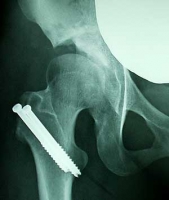

レントゲンを撮影してから診察。切った骨もだいぶ癒着してきてる様子でした。そして両松葉杖から片松葉杖の許可がでました。

全体レントゲン画像は「治療記-レントゲン画像」にアップしました。